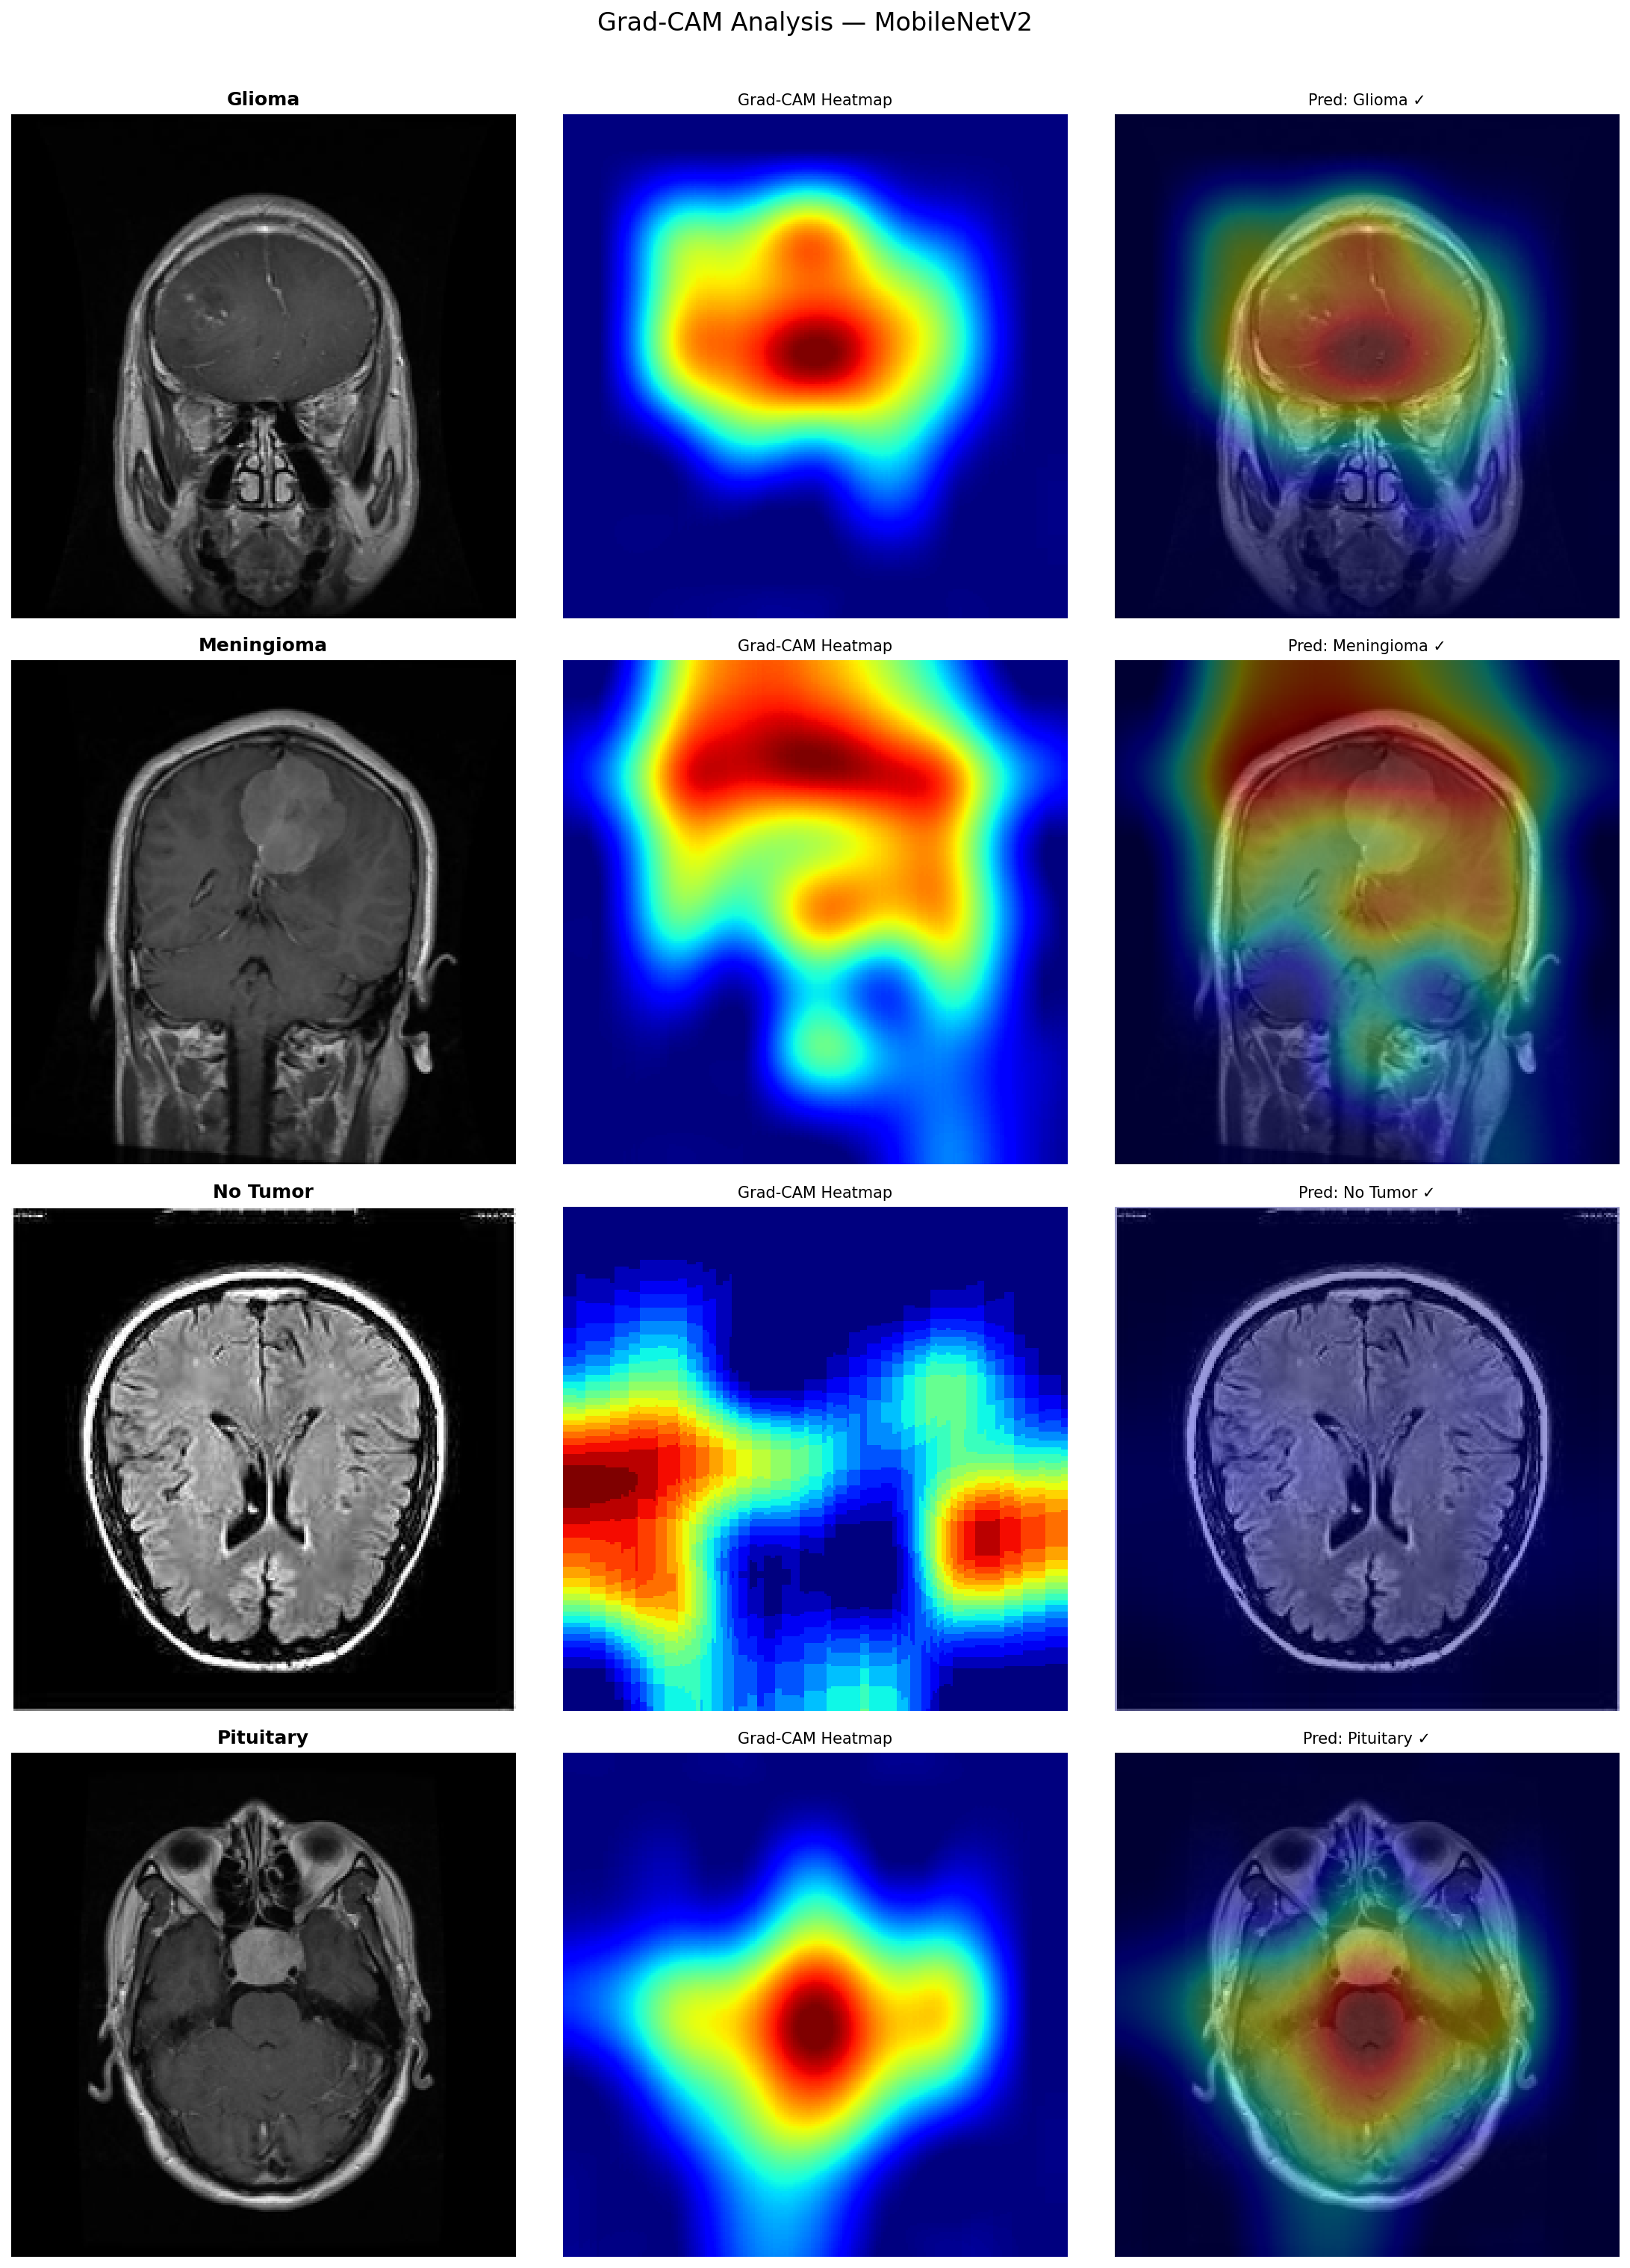

What Happens When You Ask an AI to Show Its WorkContinue reading on Medium »

A Window Into the Black Box